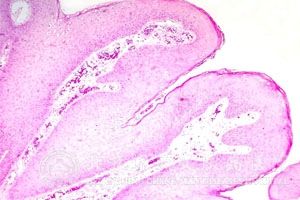

生殖器疱疹临床分原发性和复发性两种,复发性生殖器生殖器疱疹分发作期和非发作期两个阶段浸洗治疗。所以治疗应按不同临床表现和阶段浸洗辩证诊治,分型治疗。总的原则是

1、原发性疱疹应积极治疗,防治复发。治疗适宜使用类药物。

2、复发性生殖器疱疹在发作期应以祛湿为主,佐以扶正。非发作期应以滋补肝胃、益气健脾。扶正为主

3、对于复发次数频繁,症状较重的病人可中西医结合浸洗治疗。

4、生殖器疱疹糜烂时,可内外结合,加速皮疹愈合